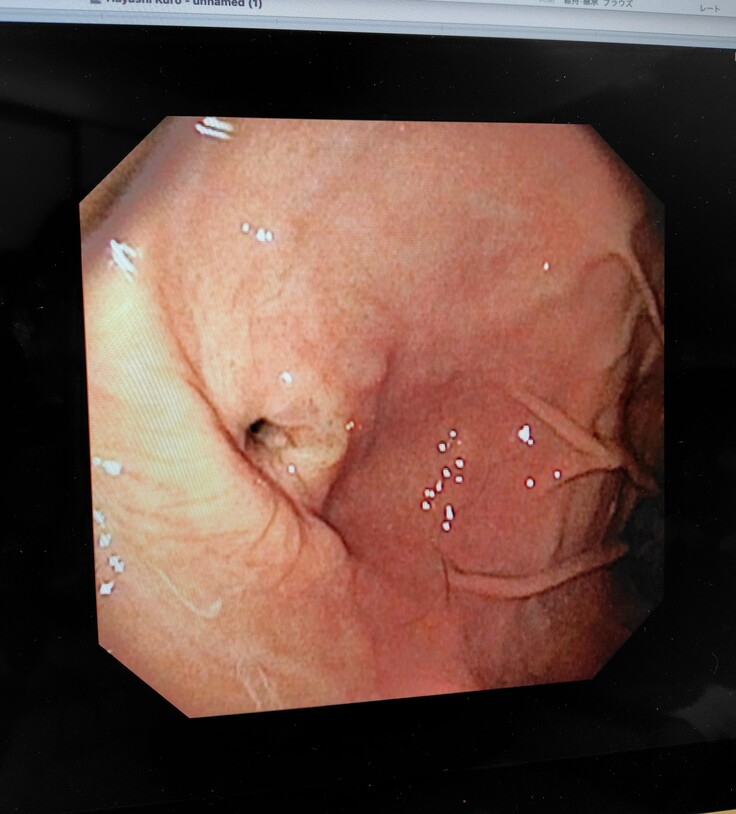

麻酔をし、内視鏡にて再度食道や胃の様子を確認され、食道の手術跡も順調に回復していたようです。胃瘻チューブの穴は医療用ボンドにて埋められそのうち塞がるとの事でした。先生に連れられて出てきてくれましたが、胃瘻チューブも取れてスッキリしてとても気分も良さそうでした😂

食道や胃もキレイな状態です😄本当に手術をしたのかなと思うくらい回復が早いです😄